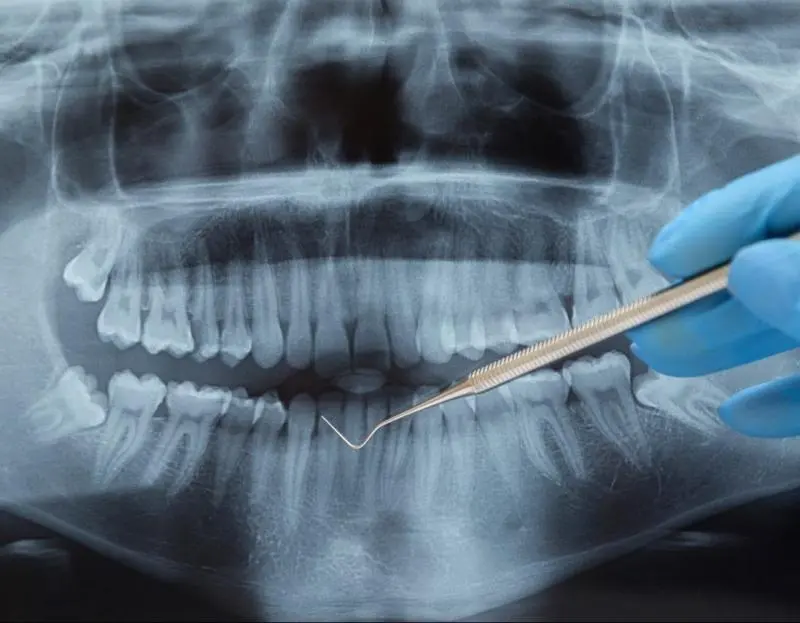

Die zahnärztliche Chirurgie umfasst alle operativen Eingriffe im Mundraum. Es handelt sich also um Operationen, die die Zähne, den Kiefer und die Weichgewebe der Mundhöhle betreffen. Das Spektrum reicht von der Entfernung von Weisheitszähnen bis zu Implantationen und der chirurgischen Parodontitisbehandlung u.v.m.

Weitere mögliche Eingriffe in der zahnärztlichen Chirurgie sind die operative Freilegung retinierter (nicht vollkommen durchgebrochener) Zähne, Zahnextraktionen bei Kieferorthopädie, die Wurzelspitzenresektion, der plastische Kieferhöhlenverschluss, die Entfernung von Zysten und gutartigen Kiefertumoren, die plastische Laser-Korrektur am Zahnfleisch und den Schleimhäuten und die Schleimhaut- und Knochenbiopsie als diagnostische Gewebeprobe.